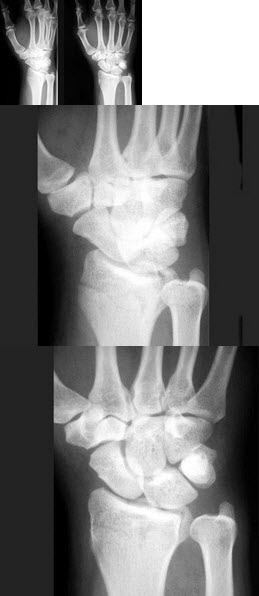

194、单项选择题

女,55岁,跌倒后右手痛,结合X线平片表现,正确的诊断是()

A.柯莱斯骨折

B.蒙泰贾骨折

C.加莱阿齐骨折

D.尺桡骨骨折

E.反柯莱阿齐骨折